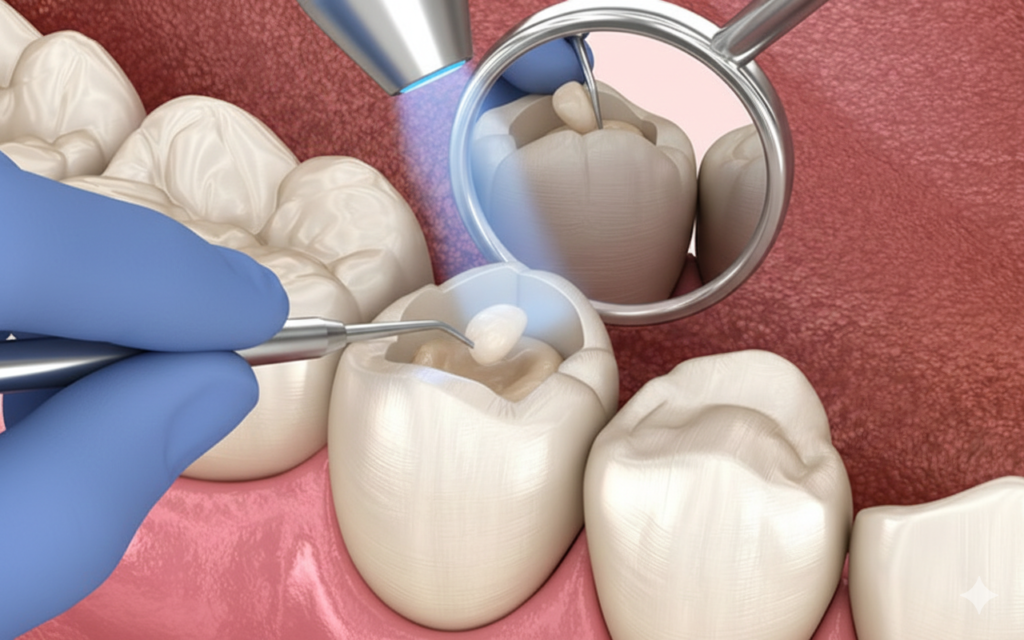

Kunstofffüllungen

Moderne Kunststofffüllungen aus hochwertigem Komposit ermöglichen eine ästhetisch perfekte und nahezu unsichtbare Reparatur von kleineren Kariesdefekten direkt im Zahn. Dank ihrer speziellen Materialeigenschaften werden sie schichtweise verarbeitet und stabil mit der natürlichen Zahnsubstanz verbunden, um eine langlebige und belastbare Versorgung zu gewährleisten.